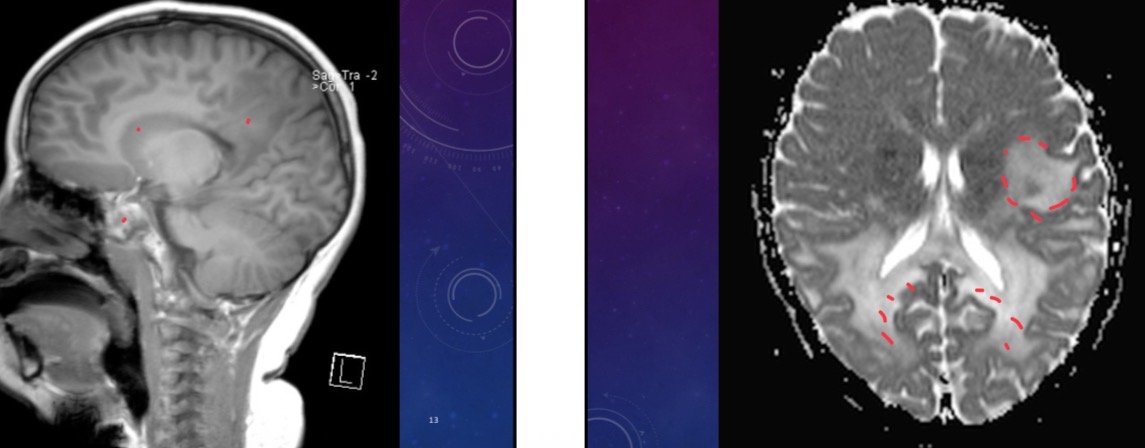

20 year-old female presents with tremor and dystonia

Panda sign = Wilson disease aka hepatolenticular degeneration

20 year-old female presents with convulsions

Neurocysticercosis - vesicular stage

55-year-old female presents with occipital headaches and neck stiffness

Thrombosed Aneurysm of postero-inferior cerebellar artery